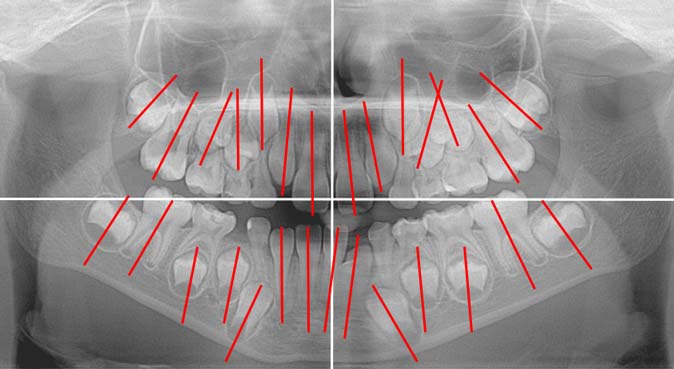

На ортопантомограмме направление прорезывания зачатков постоянных зубов было нарушено, выявлен недостаток места в дуге для прорезывания боковых резцов (рис. 2).

Рис. 2. Ортопантомограмма пациента Л., возраст 8 лет 6 мес

В возрасте 12 лет по причине задержки прорезывания постоянных зубов и неравномерной резорбции корней временных моляров [28] пациент был направлен на ортопантомографию и удаление временных зубов (рис. 3).

Рис. 3. Ортопантомограмма пациента Л. 12 лет